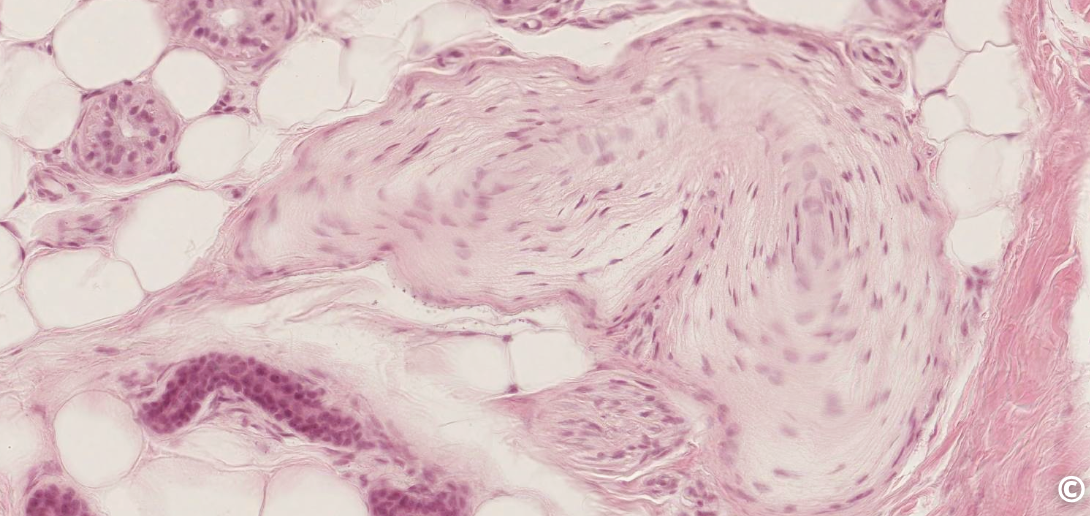

<p>what this</p>

what this

lamellar (Pacinian) corpuscle